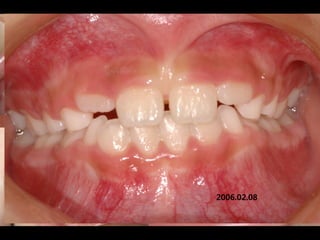

2006.02.08

2004.05.13

1999.04.05/F

C.C

• Diastema, flattened lower ant.

Dx

• Mentalis action, heavy labial frenum

Goal

• Establish normal lip tone